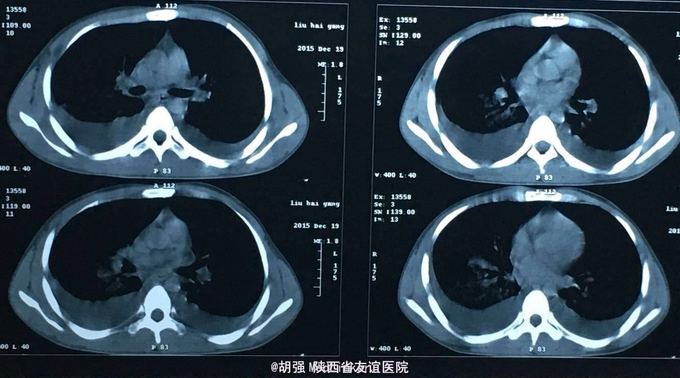

20岁男性患者,主诉:发热2月。 现病史:患者于2月前无明显诱因出现咽痛伴发热,测体温最高为40摄氏度,发热前有寒战,发热无规律,无咳嗽、咳痰,无胸痛、咯血、盗汗,无胸闷、气短,于当地医院诊断为:化脓性扁桃体炎,给予抗感染治疗后体温有所下降,未重视及进一步治疗。2天前无明显诱因出现咳嗽、咳少量暗红色血痰,伴胸痛、气短遂来我院。近1周食纳差。

查体:口唇无发绀,咽充血,双侧扁桃体2度大,表面可见脓胎。两肺呼吸音粗糙,可闻及管状呼吸音。余查体无明显异常。 辅助检查:血常规提示白细胞及血小板明显低于正常值,肝功提示转氨酶升高。凝血系列:PT、APTT时间明显延长。T sport试验弱阳性。10月份胸部CT平扫未见明显异常。10月26日及12月12日胸片未见明显异常。12月19日胸部CT提示:两肺斑片状阴影,两侧胸腔积液。